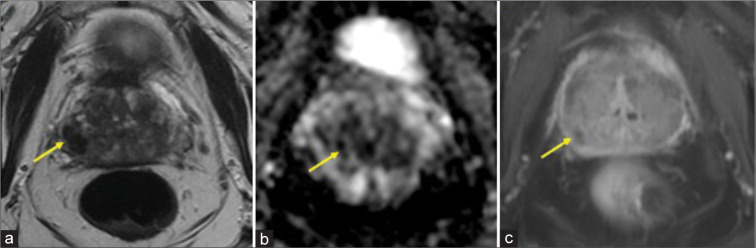

Granulomatous prostatitis (GP) is a rare form of chronic prostatitis with reported incidence of 0.65-1.5%. Radiological features of GP overlap with those of prostate adenocarcinoma. The following magnetic resonance imaging characteristics can suggest the diagnosis in an appropriate clinical setting: Diffuse or focal nodular low T2 signal, high signal on diffusion-weighted imaging with corresponding low apparent diffusion coefficient signal, and post-contrast imaging with lesion enhancement or rim-enhancing in the setting of caseous necrosis or abscess formation. Even with suspicion on imaging, the overlapping imaging features with prostate adenocarcinoma necessitate biopsy for confirmatory diagnosis. Here, we report a case of a 70-year-old man with GP in the setting of prior intravesicle bacillus Calmette-Guérin administration.